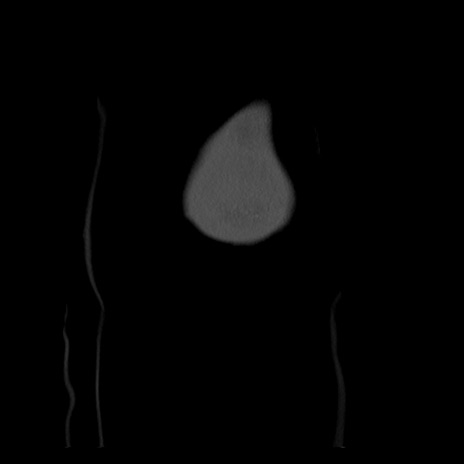

右膝関節レントゲン

正面像